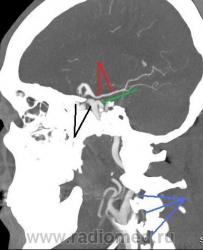

Мужчина, 62 года. Перенес ишемический инсульт в бассейне правой средней мозговой артерии.

На КТ-ангиографии выявлена окклюзия правой внутренней сонной артерии в области развилки в виде паламени свечи (красная стрелка), стеноз высокой степени в устье правой вертебральной артерии (желтая стрелка), небольшой перегиб в устье левой вертебральной артерии (голубая стрелка).